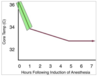

The airway pressure in this waveform clearly depicts dynamic hyperinflation, otherwise known as breath stacking. Patients with COPD have a longer expiratory time constant, and this means they require a longer period of time to exhale fully.

Of the answer choices provided, there are two options that reverse dynamic hyperinflation. By reducing the respiratory rate, the patient will spend more time over the course of a minute in E time. If PEEP becomes dangerously elevated, the definitive treatment for dynamic hyperinflation is to remove the patient from the ventilator.

Increasing inspiratory time is another way of saying reducing expiratory time, so this choice will actually make the patient’s condition worse. The inspiratory flow determines how fast the tidal volume is delivered to the patient. Increasing the inspiratory flow will deliver the preset tidal volume faster, and this does nothing to facilitate expiration.

A patient with COPD is mechanically ventilated. Which interventions will improve this patient’s condition? (Select 2.)

Decrease respiratory rate.

Disconnect the circuit.

Increase inspiratory flow.

Increase inspiratory time.

Decrease respiratory rate

Disconnect the circuit